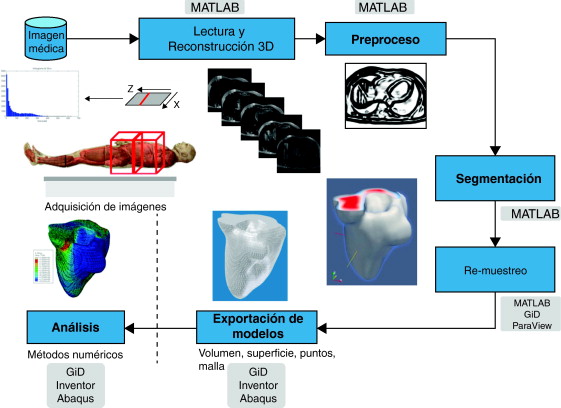

En este trabajo se define una metodología eficiente para la obtención de modelos geométricos de tejidos del cuerpo humano a partir de las imágenes médicas, los cuales resulten útiles para su mallado y el análisis de su comportamiento con métodos numéricos como los Elementos Finitos (FEM). Esta metodología propone el uso de un conjunto de rutinas de procesamiento digital de imágenes y su adecuada combinación para cada etapa implicada en la obtención de modelos geométricos del cuerpo humano, las cuales fueron implementadas en una herramienta computacional desarrollada en MATLAB [12] con una interfaz de usuario que permitió configurar los parámetros y procesos dependiendo del tejido bajo estudio. Las etapas de procesamiento consideradas son: la etapa de lectura y reconstrucción de imágenes 3D, preproceso, segmentación, remuestreo, y exportación de modelos en formatos legibles por herramientas de visualización médica o CAD. Para la validación de la funcionalidad de las rutinas se consideraron dos criterios: los tiempos de ejecución y la precisión de los volúmenes obtenidos, para lo cual se aplicó el análisis de texturas a través de descriptores estadísticos calculados en la matriz 3D de los volúmenes generados.

2. Conceptualización y metodología

El problema de obtener modelos geométricos a partir de imágenes médicas implica la utilización de un conjunto de rutinas de procesamiento aplicadas a la matriz 3D de las imágenes médicas a lo largo de varias etapas de procesamiento. En la figura 1 se observan las cinco etapas propuestas con las herramientas de software utilizadas en cada una de ellas, las cuales son: (1) etapa de lectura y reconstrucción, en la cual se implementó una rutina para obtener una imagen 3D de dimensiones m × n × o obtenida por el apilamiento paralelo de o cortes ortogonales (axial, coronal o sagital) del mismo tamaño de m × n pixels , donde cada elemento de la matriz representa un valor de intensidad de gris calculado por la interacción de la radiación en el tejido. (2) Preproceso, en la cual se aplicaron rutinas de suavizado de ruido y realzado de bordes, de este modo se mejoró la calidad de las imágenes, preparándolas para la siguiente etapa. (3) Segmentación, en la cual se utilizaron rutinas de extracción del volumen de los tejidos u órganos de interés. (4) Remuestreo, donde se emplearon rutinas de posprocesamiento para suavizar las superficies y eliminar elementos no conectados presentes en los volúmenes segmentados. (5) Exportación de modelos, para lo cual se implementaron rutinas para almacenar los volúmenes obtenidos en formatos legibles por herramientas de visualización médica y CAD, en las cuales se visualice en sólidos, superficies, mallas, etc.

Figura 1. Esquema de procesos y rutinas implementados en una herramienta de procesamiento de imágenes médicas desarrollada en MATLAB [13] . |

Para la obtención de los modelos geométricos y la interacción con los algoritmos de procesamiento considerados en este trabajo, se desarrolló una herramienta computacional [13] bajo la plataforma de MATLAB [12] , en la cual se integraron las rutinas por etapas (fig. 1 ).

A continuación se describen los algoritmos de procesamiento considerados por cada una de estas etapas, y como fueron implementados en este trabajo.